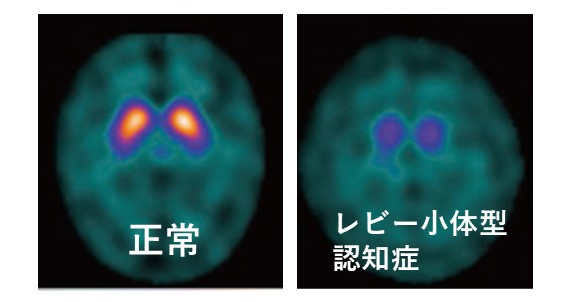

DaTSCAN(ダットスキャン)

核医学検査の一種です。脳内のドパミン神経の減少を評価することができます。レビー小体型認知症やパーキンソン病では集積が低下していますが、アルツハイマー病では正常なことが多いです。両者の診断に役立ちます。

ダットスキャン